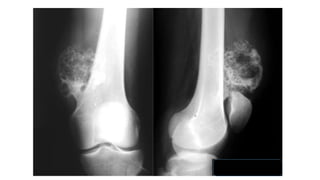

OSTEOCONDROMA

Osteocondroma .- Consideraciones Generales

•El osteocondroma es el tumor óseo benigno más común y la neoplasia

esquelética más común

o Representan aproximadamente el 35% de todos los tumores óseos benignos

y el 9% de todos los tumores óseos

•Son proyecciones óseas cubiertas de cartílago de la superficie externa de un

hueso

•Se encuentran con mayor frecuencia alrededor de la rodilla (40%) y del hombro,

aunque pueden aparecer en cualquier hueso.

•Casi todos se diagnostican en pacientes menores de 20 años con un marcado

predominio masculino: femenino (3: 1)

•Crecen hasta la madurez esquelética y luego dejan de crecer cuando se fusiona

la placa epifisaria, Los osteocondromas tienden a aparecer cerca de una placa de

crecimiento epifisario y se alejan de la fisis

OSTEOCONDROMATOSIS

MÚLTIPLE EN NIÑA DE

13A.